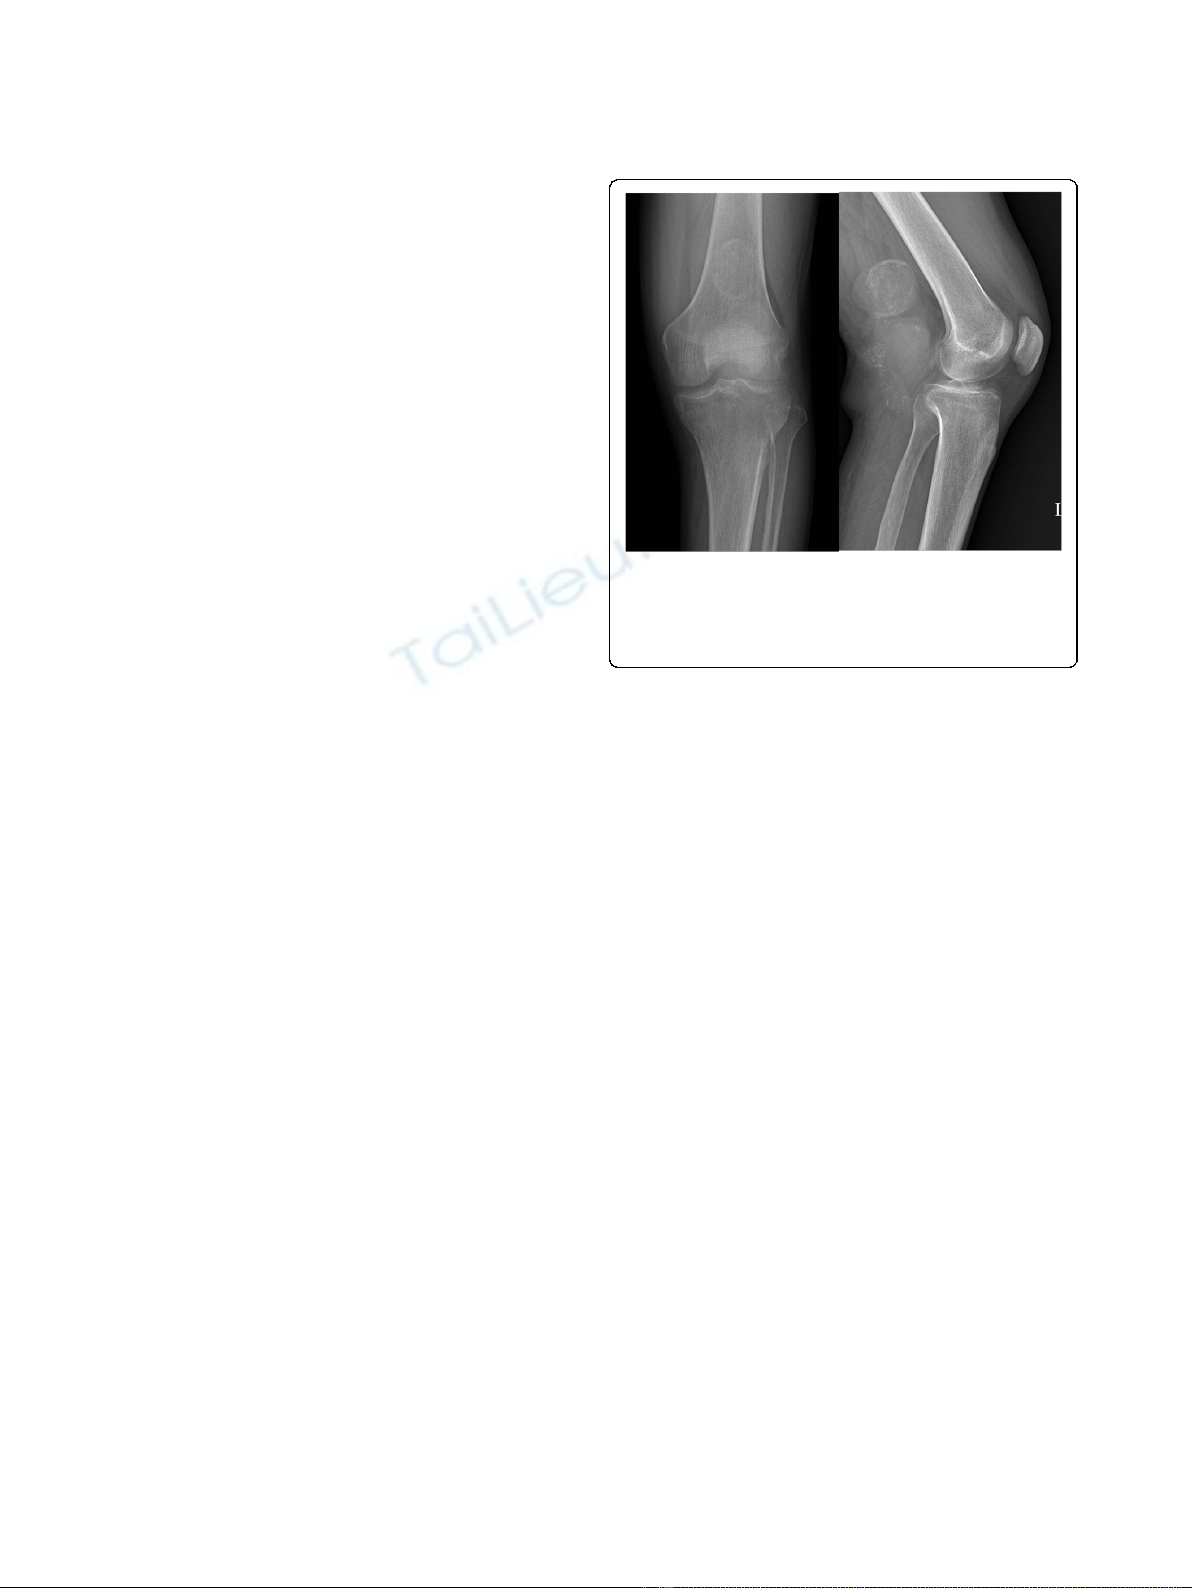

tumor location several times over 20 years. No common

characteristic findings were evident by plain radiography,

although one case of synovial sarcoma (Figure 1) and one

case of alveolar soft part sarcoma showed calcification on

Figure 1 A plain radiograph showing a well-defined soft tissue

mass with marginal calcification posterior to the distal femur.

There is no evidence of associated bone erosion in this patient. This

is an example of a synovial sarcoma in one of its more common

locations.